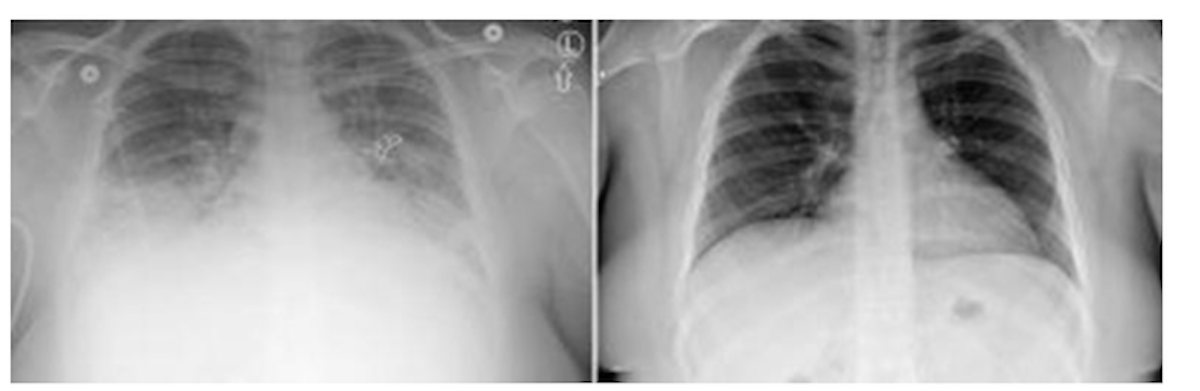

Sickened lungs show up as cloudy on the left X-ray and clear after treatment of one suspected VAPI patient in Utah. (Courtesy University of Utah)